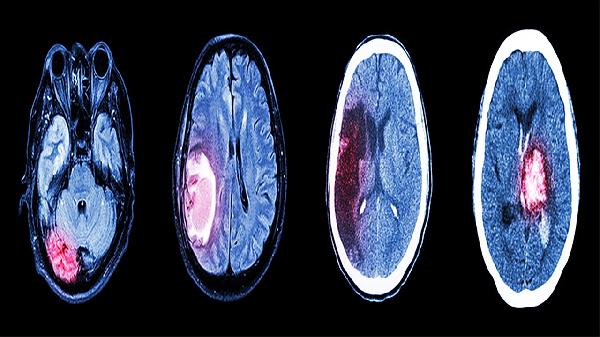

通过头颅CT或MRI检查明确缺损范围,评估脑组织受压情况。需检查凝血功能、肝肾功能等基础指标,排除手术禁忌。医生会结合三维重建技术定制个性化修补方案,选择钛网或聚醚醚酮等修补材料。